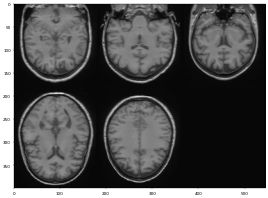

3D brain image에 대해 n4 bias field correction을 적용해보았을때의 모습이다(왼쪽 : original, 오른쪽 : processed). 자세히 살펴보면 original data에서의 low frequency를 갖는 region들이 향상이 된 부분을 볼 수 있다. (그림의 A 부분 참고)